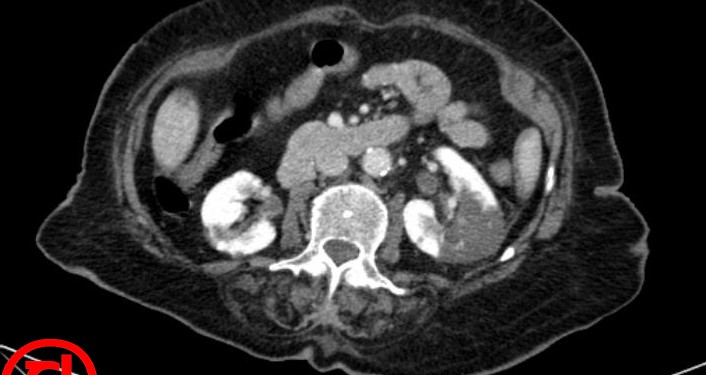

Karın ve sırt ağrısı şikayeti ile acil servise başvuran kırk beş yaşındaki erkek hastanın narkotik analjezi ile ağrısı kontrol altına alınamıyor. Bu durum acil servis içinde büyük üzüntü dalgası yaratıyor, hüzün radyolojik tetkikte meyvesini veriyor. Şekilde hastanın ilaçla beyazlatılmış iç organ tomografisi görülüyor!

Tanı: Sol renal arter trombozu( sol böbreğin %50sinde kontrast tutulumu yok).